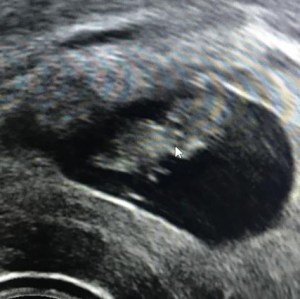

After explaining our situation to the midwife and having her narrowly stop me from taking my pants off (…old habits…), I climbed onto the exam table for my abdominal ultrasound. I was in tears before the exam even started, so conditioned by our ‘journey’ to expect the worst. But almost immediately, she told us it was good news — she could see the growing embryo!

She then asked me to remove my pants for a trans-vaginal ultrasound (see!) and she told my husband he could get out his phone. (She had told him phones weren’t allowed earlier in case it was bad news…won’t fall for that twice.) The raspberry-sized embryo was measuring right on track for its age, and we could even see a heartbeat. Despite our worst fears, everything was progressing just fine.*

Since I had such a hard time finding success stories for anything less than BB, let me add our own small success story here for those still in the trenches. Our embryo was only a 3BC (and by day 6, at that), our donor (Marie) was a month shy of 37, and while we won’t stop worrying ’til the very end, here is the 8-week scan of our bean.